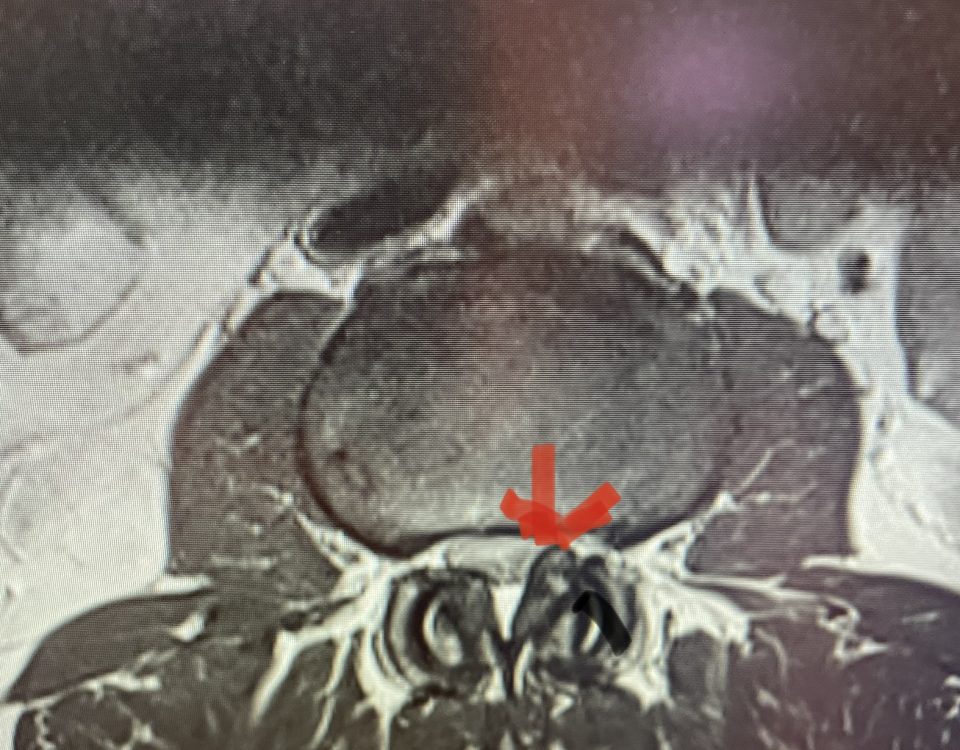

The spinal synovial cyst is one of the most interesting expressions of spinal instability. They emanate from the synovial lining of a degenerated facet joint that […]

The actual structural cause of lumbar thecal sac compression can vary in degenerative spondylolisthesis and stenosis. The culprits are commonly thickened ligamentum flavum or severe facet […]

People are obsessed with cysts! When you think about it, the body likes to form cysts. Why does this happen? Cysts can form just about anywhere […]